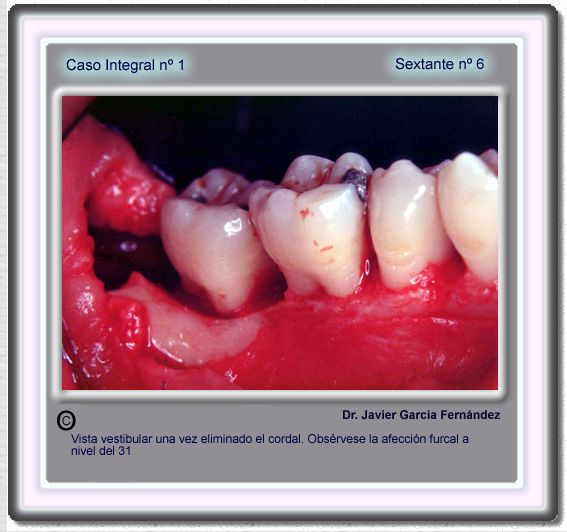

image 104